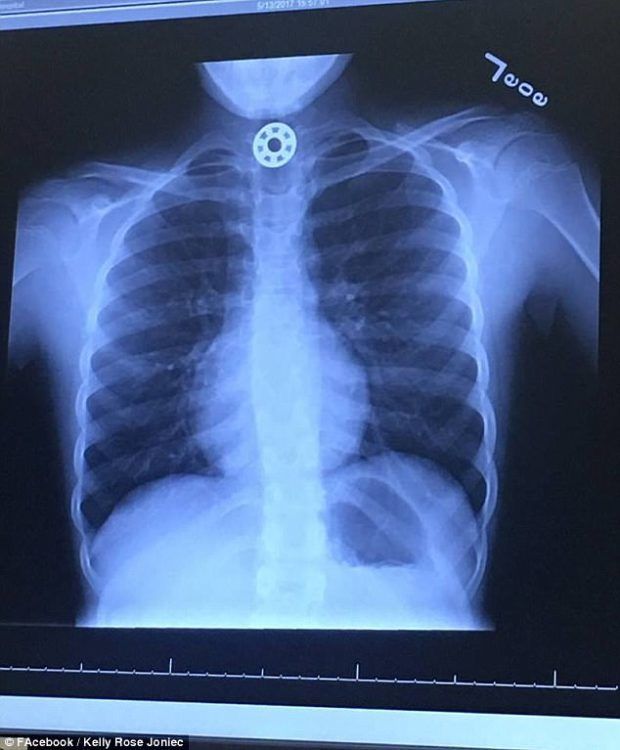

Η Kelly οδήγησε αμέσως την κόρη της στο πλησιέστερο νοσοκομείο, όπου της έκαναν ακτινογραφίες οι οποίες έδειξαν την τρομακτική θέση που είχε πάρει το κομμάτι του παιχνιδιού:

Η Britton υποβλήθηκε αμέσως σε χειρουργική επέμβαση και ευτυχώς επέζησε από την εγχείρηση.